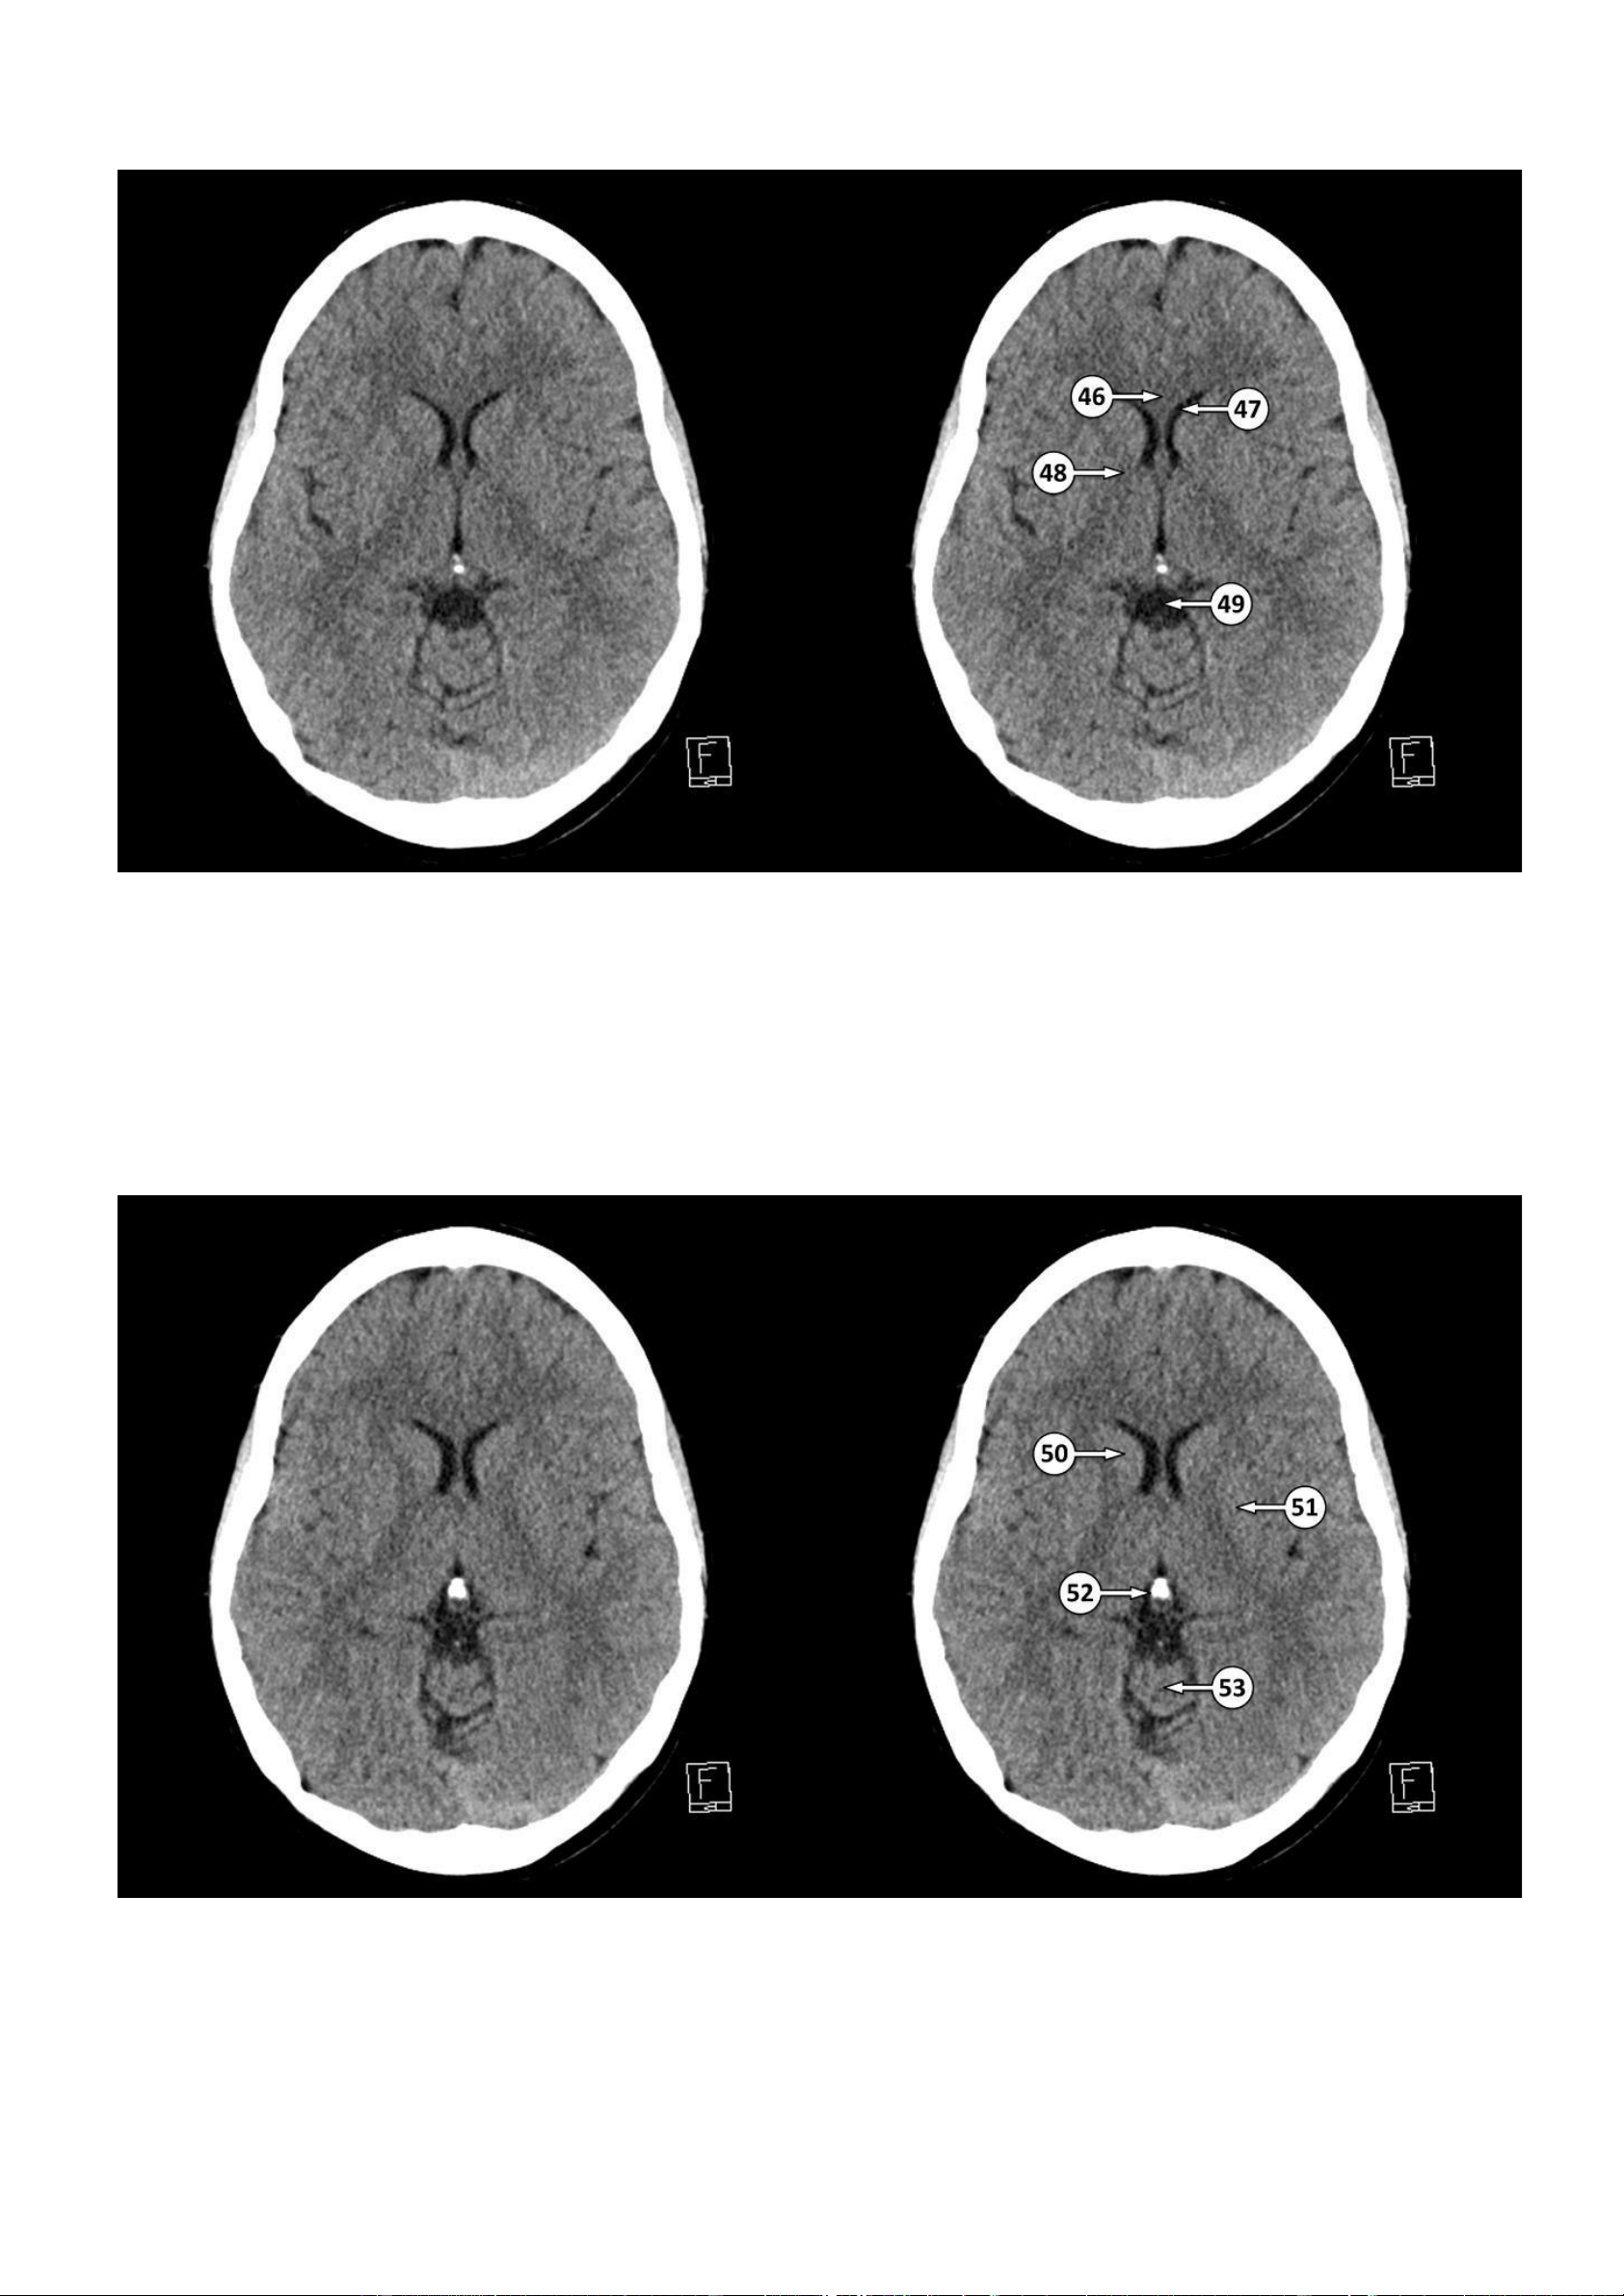

▪ Số 46: Gối của thể chai

▪ Số 47: Sừng trán của não thất bên

▪ Số 48: Gối của bao trong

▪ Số 49: Bể quanh củ não sinh tư

▪ Số 50: Đầu của nhân đuôi 51: Nhân đậu (nhân bèo) 52: Tuyến tùng lOMoAR cPSD| 22014077

Thảo Thảo & Bé Nghìn Dặm

53: Thuỳ giun trên của tiểu não

▪ Số 54: Cột của vòm não

▪ Số 55: Cánh tay sau của bao trong

▪ Số 56: Tĩnh mạch não trong ▪ Số 57: Xoang thẳng 58: Hồi đai lOMoAR cPSD| 22014077

Thảo Thảo & Bé Nghìn Dặm 59: Vách trong suốt 60: Đồi thị ▪ Số 61: Bó nhỏ